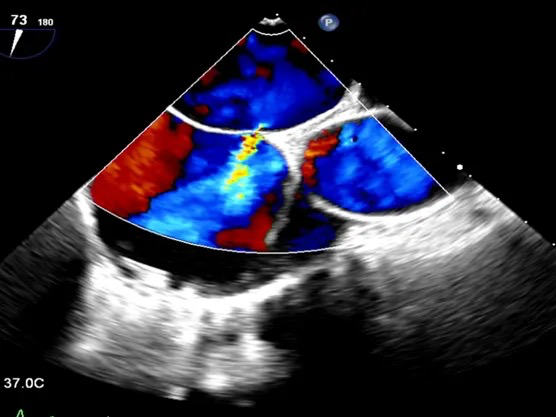

经食道心脏超声:四腔心切面缺口径宽约0.35cm,缺损边缘距二尖瓣环约2.1cm,距房顶约2.5cm,大动脉短轴切面缺口经宽0.36cm,主动脉后方无残边。双房切面缺口径约0.35cm,缺损边缘距上腔静脉约2.6cm,距下腔静脉约2.7cm。CDFI:房间隔连续中断处见左向右分流信号。

TEE可见房间隔中断出左向右分流